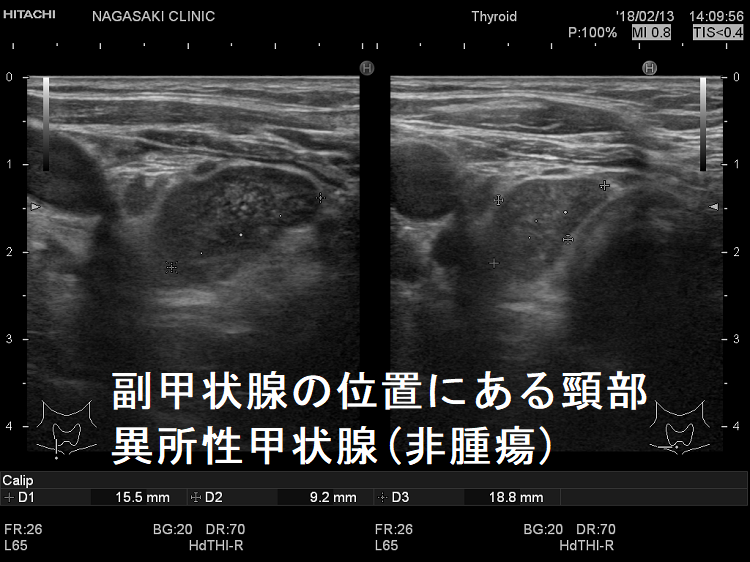

副甲状腺腺腫のように見えるも、実は異所性甲状腺

副甲状腺腺腫と同じような位置(写真では右甲状腺の下極)にあり、副甲状腺腺腫のように見えるも、実は頚部異所性甲状腺です。

副甲状腺腺腫との違いとして、頚部異所性甲状腺では

- 内部血流が甲状腺組織と同じ

- 内部の形状が甲状腺組織と同じ

です。